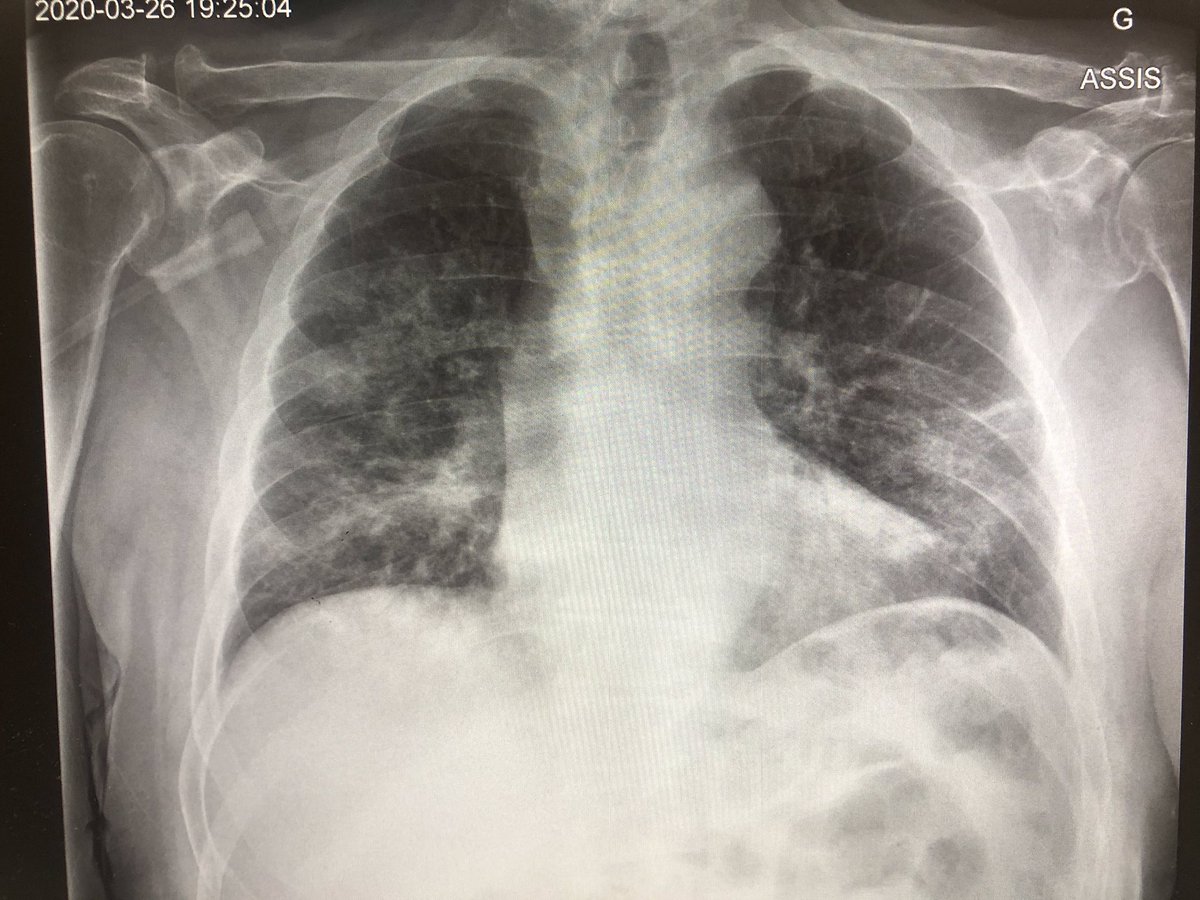

Radiographie pulmonaire. La radiographie pulmonaire permet aux médecins de visualiser les organes intrathoraciques comme les poumons, la trachée, les bronches, le médiastin et la plèvre (Double feuillet qui recouvre le poumon) L’objectif principal de cet examen est de diagnostiquer des pathologies pulmonaires. La radiographie industrielle utilise le rayonnement gamma pour détecter des défauts structurels dans des matériaux comme le métal et le béton A radiografia industrial utiliza a radiação gama para detectar falhas estruturais em materiais como metal e concreto. Bien qu’un terme de jargon soit «blanc du poumon», les raisons de cette.

Bienvenue au CENTRE D'IMAGERIE MEDICALE DE ROYAN Radiologie Générale et Dentaire Cône Beam Mammographie Ostéodensitométrie Echographie Echographie Doppler Scanner IRM radiologieroyanfr. Radiographie Une technique d’imagerie qui permet d’analyser certaines parties du corps humain grâce à l’émission de photons X – La recherche d’une maladie pulmonaire Les informations des différentes structures anatomiques traversées par le faisceau de rayonnements sont projetées dans le même plan, où elles apparaissent. Une radiographie pulmonaire est un examen d’imagerie médicale utilisé pour visualiser l’ensemble du système respiratoire à savoir les poumons, la trachée, les bronches et la plèvre La radiographie pulmonaire permet également d’étudier le cœur ainsi que les vertèbres et les côtes.

(Redirigé depuis Radiographie pulmonaire) La radiographie du thorax est une technique d' imagerie médicale à base de rayons X permettant de diagnostiquer des pathologies atteignant ou retentissant sur le thorax et ses composantes atteintes du médiastin , infections pulmonaires , pneumothorax , décompensation cardiaque, etc. RADIOGRAPHIE THORACIQUE NORMALE MariePierre Debray, Nicoletta Pasi, Yaël Amar Hôpital Bichat Tronc pulmonaire Ventricule gauche Ligne paraoesophagienne Ligne paraaortique Crosse veine azygos Médiastin et hiles pulmonaires Ligne paraaortique gauche Rayons X. Madame LT est une patiente de 47 ans qui nous a été adressée en septembre 09 après la découverte sur une radiographie pulmonaire systématique d'embauche d'une opacité basale paracardiaque droite donnant un aspect de surélévation localisée de la coupole diaphragmatique droite (Figure 1), bien visible dans sa partie antérieure sur la radiographie thoracique de profil (Figure 2).

Radiographie pulmonaire définition, déroulement de l'examen, risques pour la santé La radiographie pulmonaire est un examen d'imagerie médicale qui permet d'obtenir des images des poumons. Bienvenue au CENTRE D'IMAGERIE MEDICALE DE ROYAN Radiologie Générale et Dentaire Cône Beam Mammographie Ostéodensitométrie Echographie Echographie Doppler Scanner IRM radiologieroyanfr. Les opacités normales visibles au niveau du parenchyme pulmonaire correspondent aux vaisseaux et au tissu de soutient Savoir localiser sur une radiographie la systématisation lobaire des deux poumons on s’apeçoit ue cette systématisation est extrêmement difficile à définir de face en raison de superpositions.